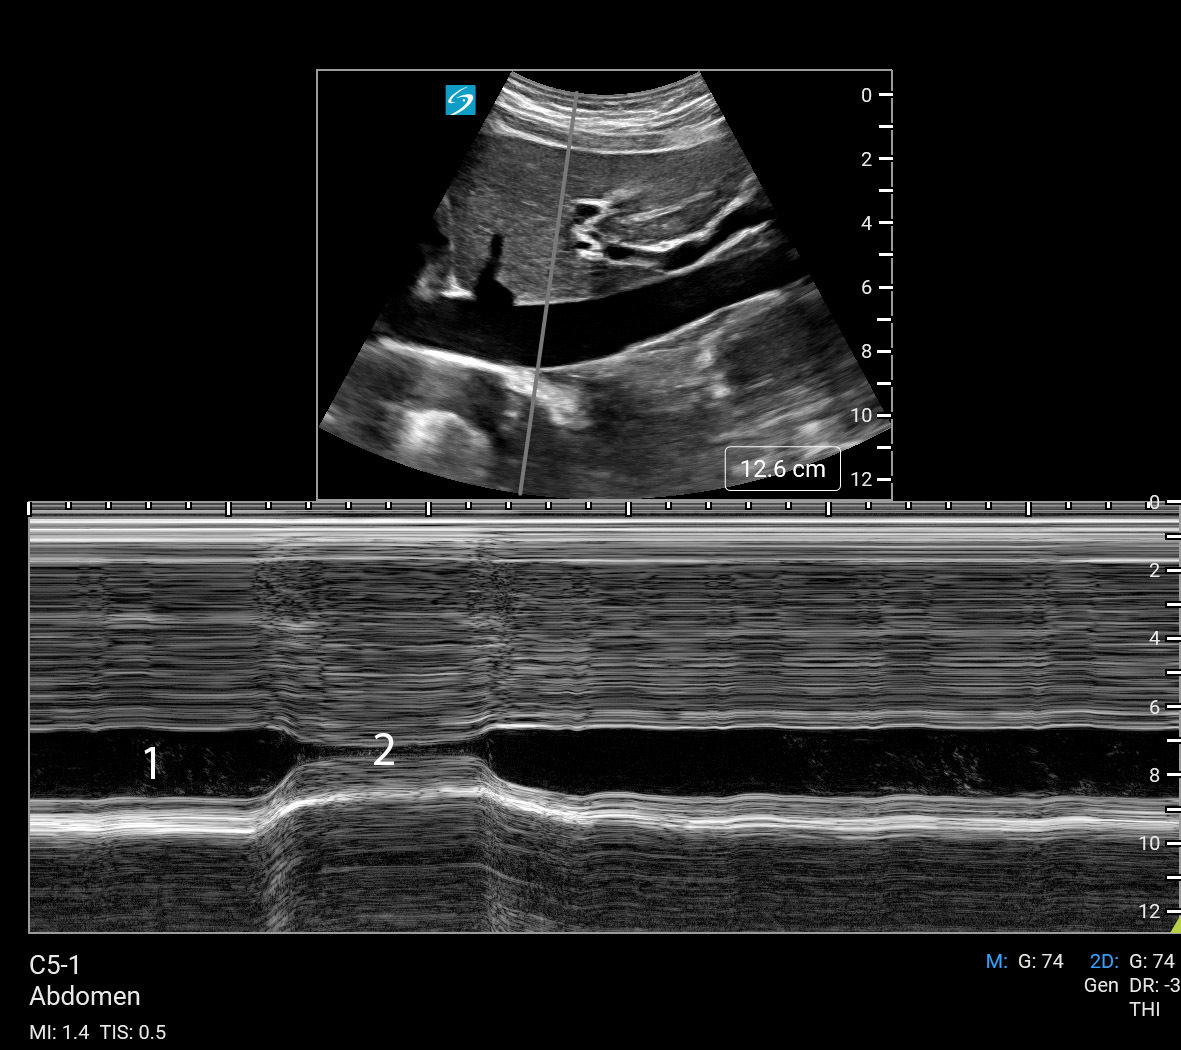

Inferior Vena Cava (IVC) Evaluation M-Mode (Sonosite PX C5-1) Image

Inspiration

Expiration